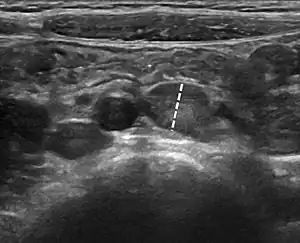

Abdominal ultrasound showing large mesenteric lymph nodes in a 6-year-old with mesenteric lymphadenitis. The largest lymph node (dashed line) measurement was 9 mm.[1]

The CT diagnosis is supported by finding more than three lymph nodes larger than 5 mm together with a normal appendix.[2]